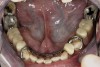

Figure 4  Intraoral occlusal view of maxillary dentition presenting excessive signs of wear.

Figure 4

Initial examination revealed a partial edentulous patient with extensive wear of the maxillary anterior teeth and moderate wear in the mandibular teeth (Figure 1, Figure 2, Figure 3, Figure 4, Figure 5, Figure 6 and Figure 7). The patient’s maxillary and mandibular RPDs also showed excessive wear and multiple signs of fractures (Figure 2 and Figure 3). The patient had been wearing a mandibular nightguard for 8 years.

A history of bruxing and consumption of acidic and carbonated drinks were reported. The clinical examination revealed severe tooth wear extending to the cervical level of the palatal surfaces of the maxillary teeth in some areas. Therefore, TSL was diagnosed as being caused by a combination of attrition and erosion.